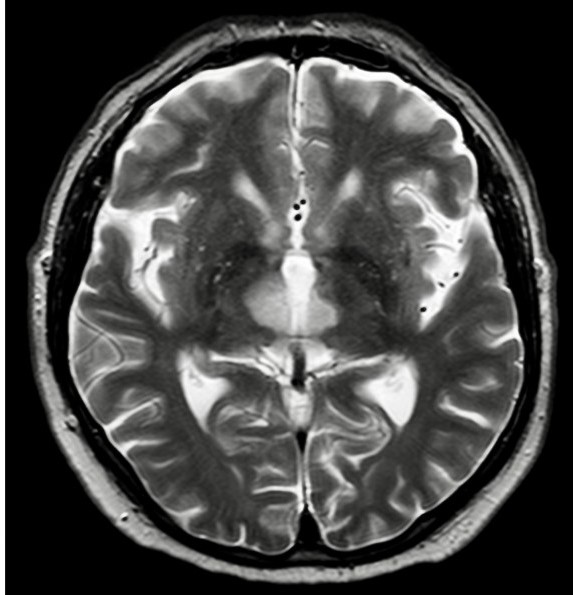

Percheron artery occlusion results in bilateral thalamic infarcts, a rare condition. It is rarely possible to detect arterial occlusion with diagnostic imaging, and diagnosis is made indirectly through findings of bilateral infarcts in the medial thalamus, with or without affection of the mesencephalon (2).

Our patient was a man in his late sixties who abruptly lost consciousness while on holiday abroad. He was quickly collected by ambulance and driven to the nearest hospital. Thrombolytic therapy was not initiated because the cause of his loss of consciousness was unclear. He was intubated on arrival and the left pupil was observed to be more dilated than the right one. CT head and CT angiography performed on the day of admission yielded no relevant pathological findings. Head MRI on day 4 of the hospitalisation showed infarcts bilaterally in the medial thalamus (image on right).